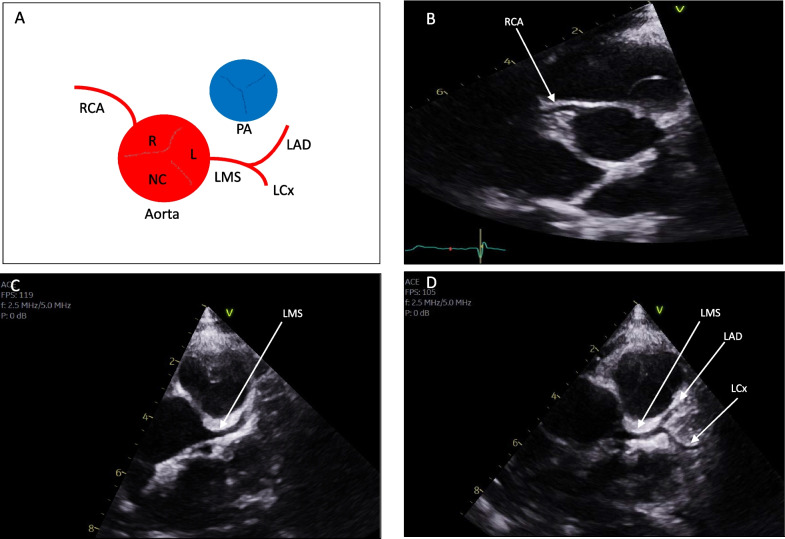

Transthoracic echocardiography is an essential and widely available diagnostic tool for assessing individuals reporting cardiovascular symptoms, monitoring those with established cardiac conditions and for preparticipation screening of athletes. While its use is well-defined in hospital and clinic settings, echocardiography is increasingly being utilised in the community, including in the rapidly expanding sub-speciality of sports cardiology. There is, however, a knowledge and practical gap in the challenging area of the assessment of coronary artery anomalies, which is an important cause of sudden cardiac death, often in asymptomatic athletic individuals. To address this, we present a step-by-step guide to facilitate the recognition and assessment of anomalous coronary arteries using transthoracic echocardiography at the bedside; whilst recognising the importance of performing dedicated cross-sectional imaging, specifically coronary computed tomography (CTCA) where clinically indicated on a case-by-case basis. This guide is intended to be useful for echocardiographers and physicians in their routine clinical practice whilst recognising that echocardiography remains a highly skill-dependent technique that relies on expertise at the bedside.